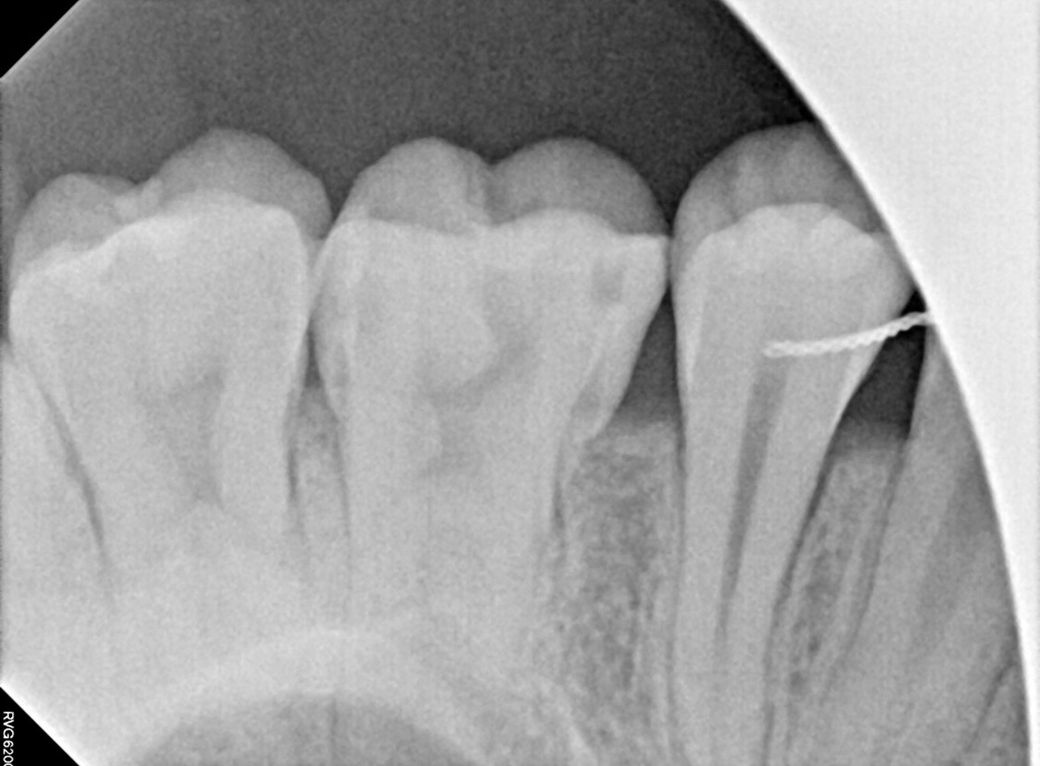

위에 쪽 앞니 하나 어금니 하나? 엑스레이 사진 찍어봤다는데 뭐가 뭔지 모르겠어서요 아마 첫번째 사진이 앞니같은데 신경치료 받아야할 정도인가요? 여기 선생님 말씀으로는 어금니는 충치가 좀 심해서 신경치료하고 크라운 씌워야한다 하셨고, 제 기준 오른쪽 앞니는 앞니 신경이 죽어있고 염증도 그래서 살짝 있다 육안으로 봤을 때도 앞니 두개 색상차이가 좀 난다 그래서 신경치료 몇회하고 크라운 해야한다 하셨는데 전 솔직히 거울 보면서 앞니 색상은 분간이 안돼서… 살면서 특별히 느낀 통증도 없었어요 참고로 신경 죽어있다는 앞니는 제가 정말 어렸을 때 깨진거고 그대로 두고 살다가 고등학생때 교정마치고 깨진부분 붙힌겁니다 세번째 사진 보시다시피 붙힌 라인에 노랗게 뭐가 낀거 마냥 변해있구요 일반 치아 마지막 사진은 윗니로 추정되는 것을 올리는 겁니다 제가 지금 윗니 교정장치가 떠서요 여기를 의심하는 건 아니고 다른 치과 의사분들 의견이 궁금합니다 추가질문 더더 하셔도 돼요 신경치료 무서워요… 대충 달지 말아주세요ㅠ 진지하게 봐주셨음 합니다

앞니의 경우에는 엑스레이 상으로 치아 뿌리끝에 염증이 있어 보입니다. 신경치료가 필요 할것같습니다. 어금니의 경우는 충치가 깊어 보이진 않습니다.

2. 엑스레이상 어금니도 충치가 있어보이긴 하는데 아주 깊거나 그렇진 않습니다